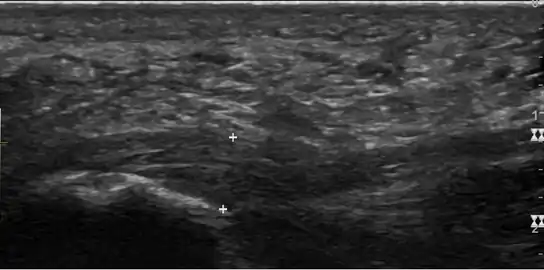

Plantar fasciitis is usually diagnosed by a health care provider after consideration of a person's presenting history, risk factors, and clinical examination.[4][16][17] Palpation along the inner aspect of the heel bone on the sole may elicit tenderness during the physical examination.[4][11] The foot may have limited dorsiflexion due to excessive tightness of the calf muscles or the Achilles tendon.[7] Dorsiflexion of the foot may elicit the pain due to stretching of the plantar fascia with this motion.[4][12] Diagnostic imaging studies are not usually needed to diagnose plantar fasciitis.[7] Occasionally, a physician may decide imaging studies (such as X-rays, diagnostic ultrasound, or MRI) are warranted to rule out serious causes of foot pain.

Medical imaging is not routinely needed. It is expensive and does not typically change how plantar fasciitis is managed.[15] When the diagnosis is not clinically apparent, lateral view X-rays of the ankle are the recommended imaging modality to assess for other causes of heel pain, such as stress fractures or bone spur development.[7]

The plantar fascia has three fascicles-the central fascicle being the thickest at 4 mm, the lateral fascicle at 2 mm, and the medial less than a millimeter thick.[18] In theory, plantar fasciitis becomes more likely as the plantar fascia's thickness at the calcaneal insertion increases. A thickness of more than 4.5 mm ultrasound and 4 mm on MRI are useful for diagnosis.[19] Other imaging findings, such as thickening of the plantar aponeurosis, are nonspecific and have limited usefulness in diagnosing plantar fasciitis.[13]